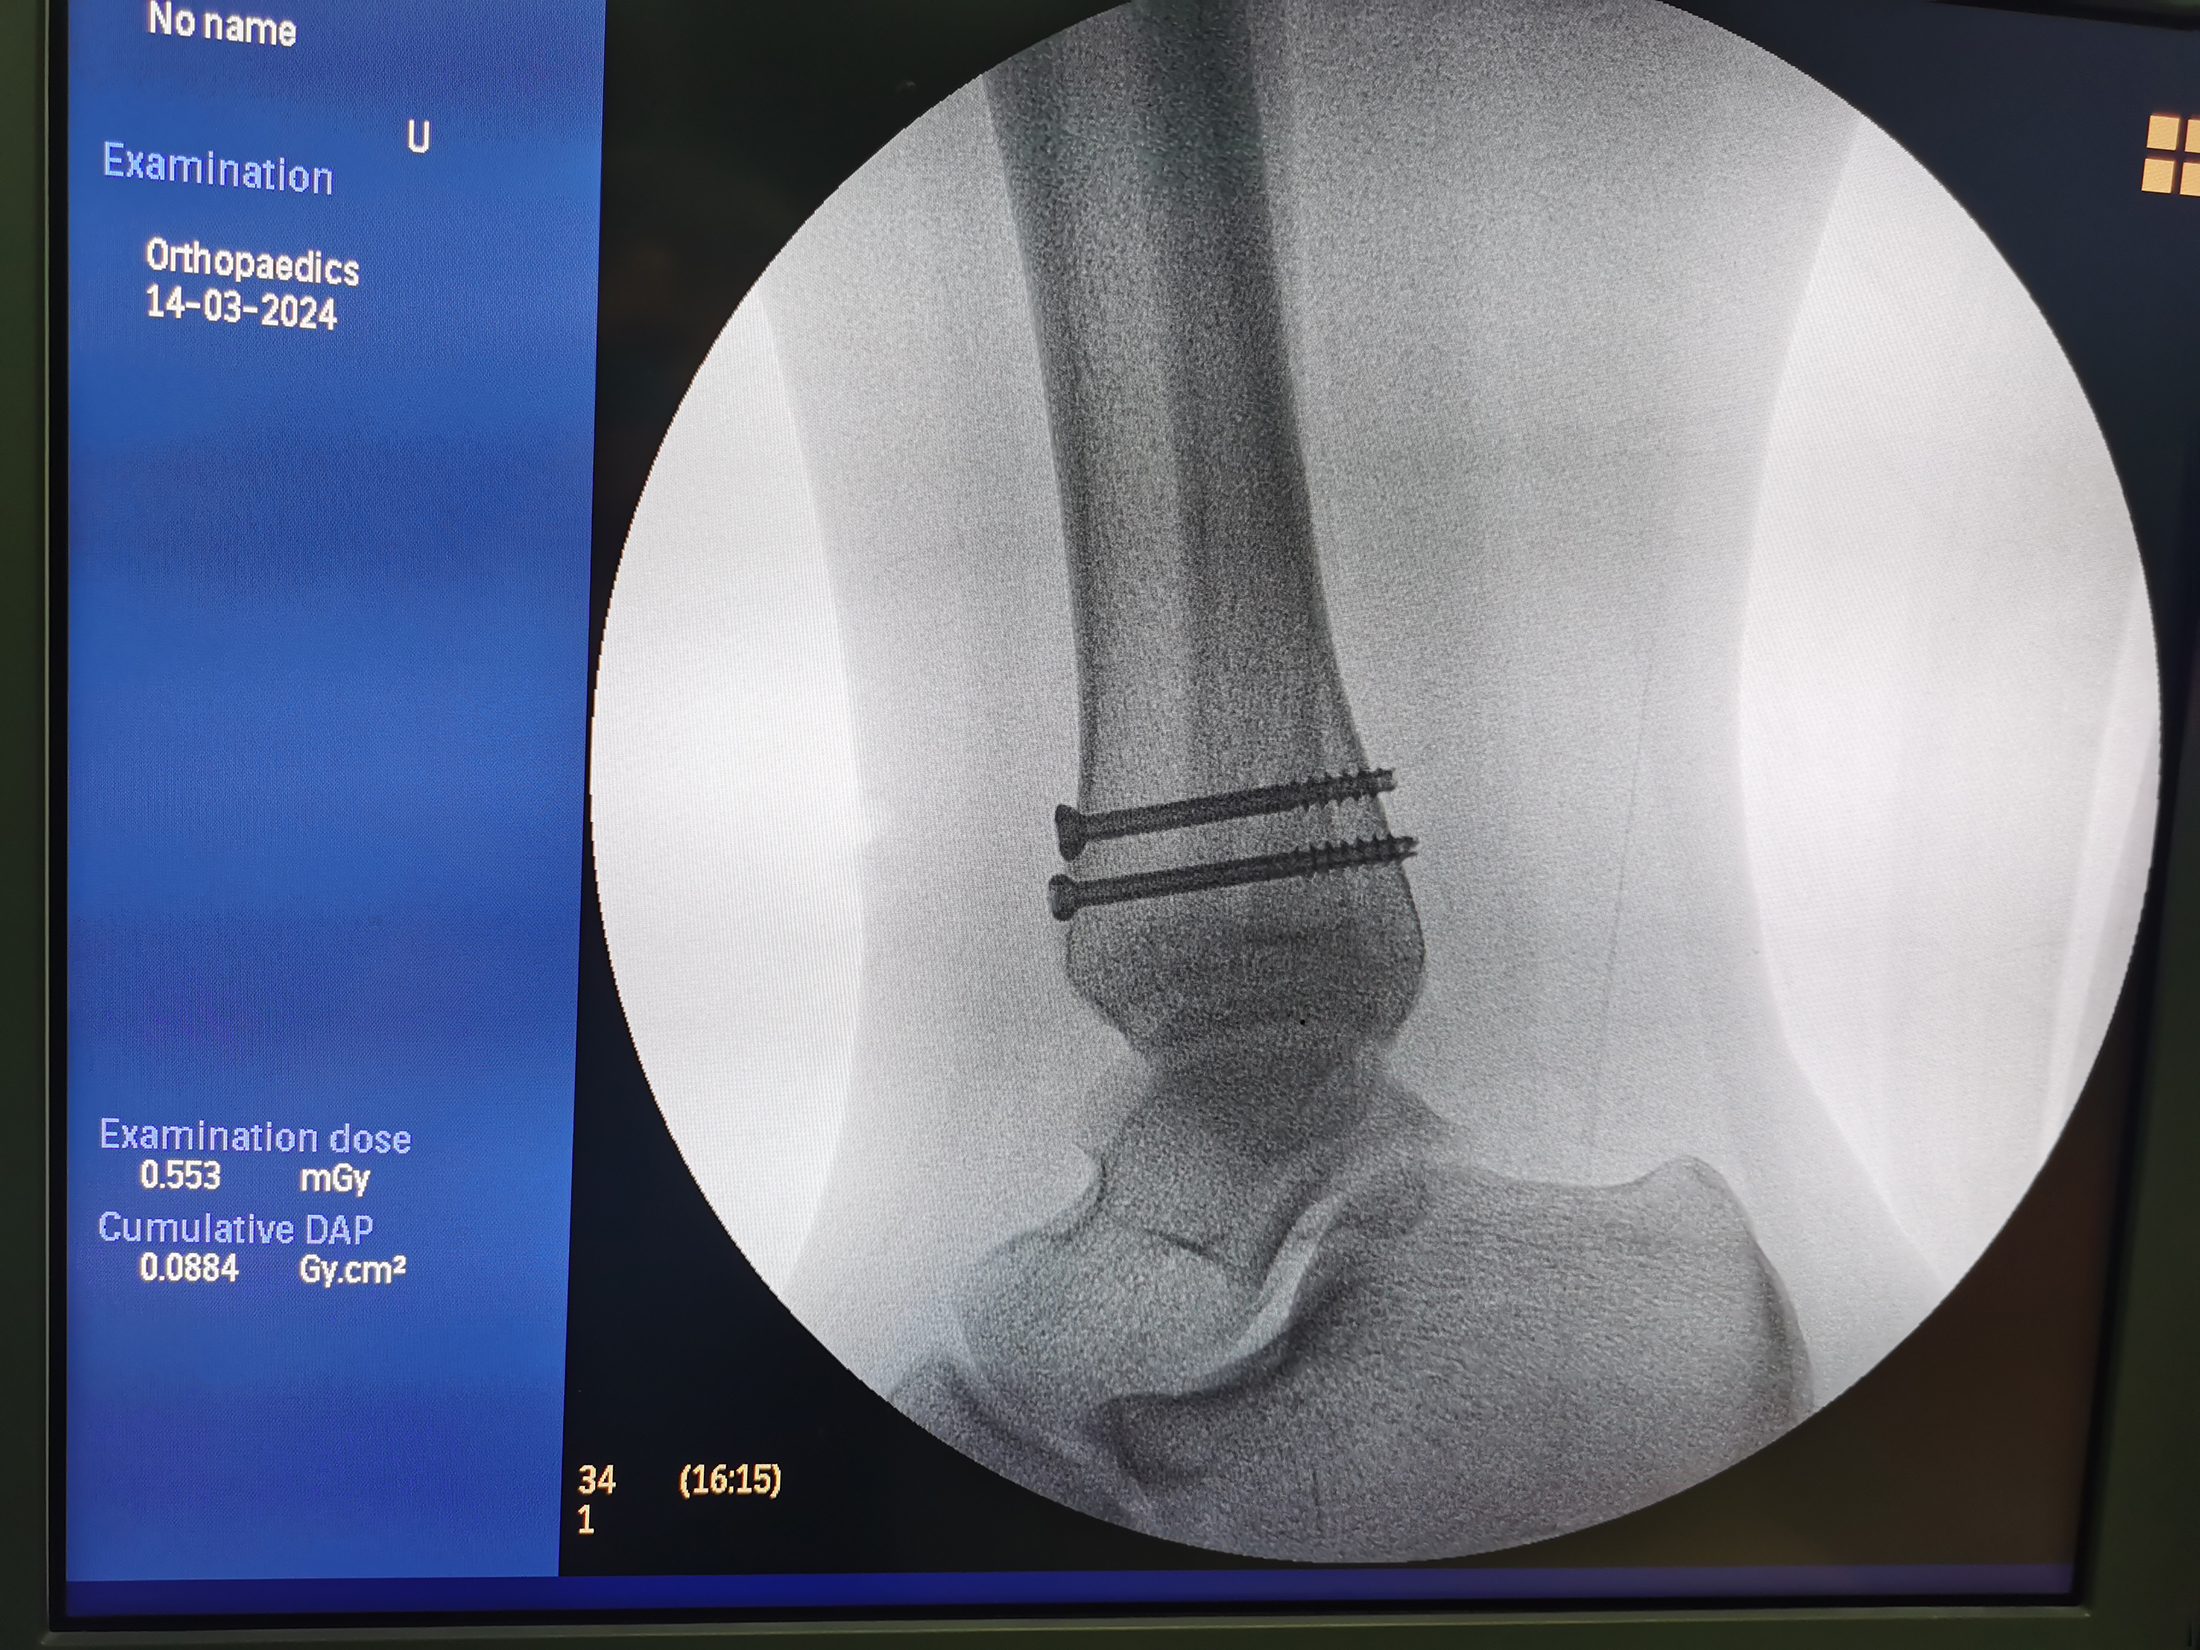

当天下午,完善术前相关检查,确保患儿凝血功能正常后,祝振华主任带领小儿外科团队为小涵实施手术。术中,祝振华主任在C臂机透视下进行手法复位,复位稳定后先予2枚直径为2mm的粗克氏针临时固定,再用两枚直径为1mm的细导向针从踝前经皮穿过骨折端,并在C臂机透视下确认骨折复位满意、克氏针在位有效,长度和位置合适后,适当在细导针周围切开小口,能使直径4mm的空心螺钉沿着导针逐步拧入患儿皮肤、皮下组织,直至螺钉头部到达骨皮质表面,利用空心螺钉半螺纹的拉力作用,将后倾移位的踝关节微创下恢复,创造更有利于骨折愈合的环境。历时55分钟,手术顺利完成,术中几乎没有出血。